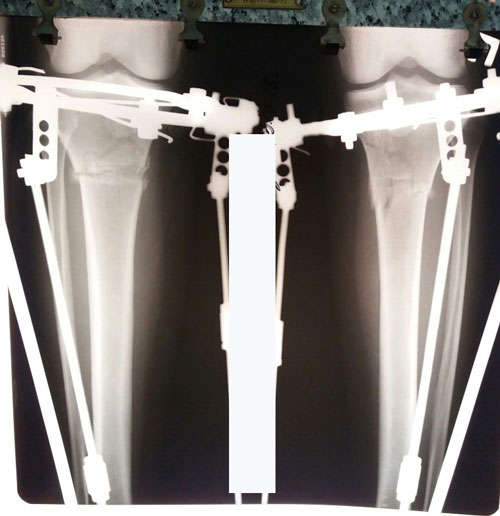

Дата операции 20.07.2018г.

Дата снятия аппаратов 04.10.2018г.

Срок сращения 74 дня.